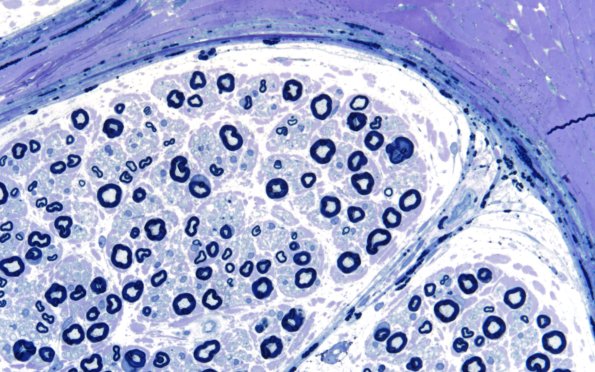

1A4 Fabry Dz (Case 1) 60X

There may be a preferential relative loss of small myelinated axons. (plastic sections)